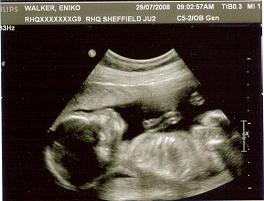

Mi is jól vagyunk. Olivér már hatalmasakat rúg, szinte az egész hasam hullámzik, deformálódik, nagyon mulatságos. Van, hogy egész délelőtt szórakoztat és én meg csak ülök a fotelban és nézem a hasam, beszélgetek neki és nagyokat nevetek

Sosem gondoltam, hogy ez lesz eddigi életem legjobb érzése. De az tuti, hogy mindig bent marad a top3-ban.